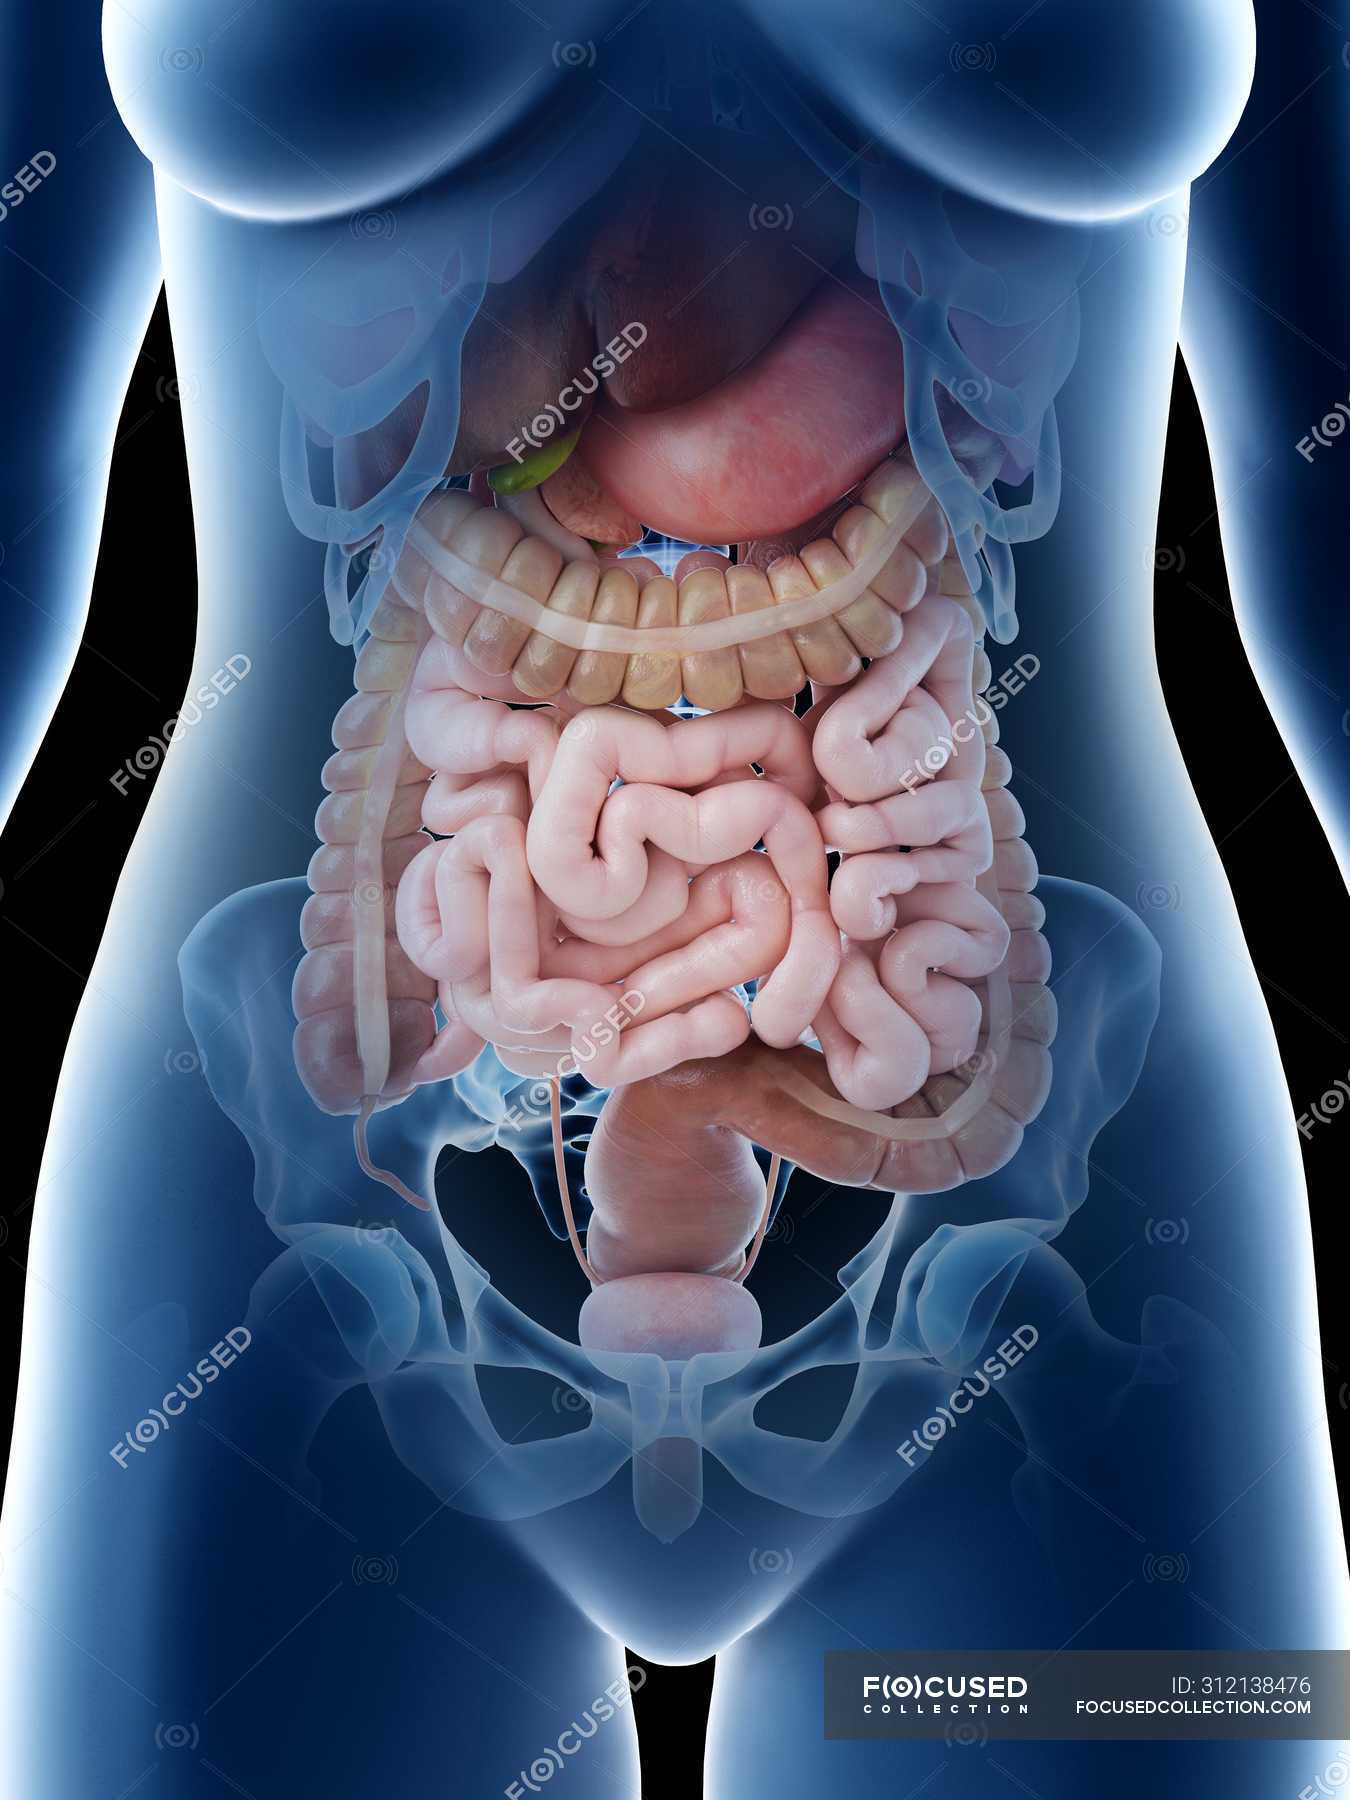

www.wallpaperflare.com3d Rendered Illustration Of A Females Abdominal Anatomy Stock Photo - Alamy

www.wallpaperflare.com3d Rendered Illustration Of A Females Abdominal Anatomy Stock Photo - Alamy

www.alamy.comanatomy 3d abdominal female illustration alamy females rendered

www.alamy.comanatomy 3d abdominal female illustration alamy females rendered